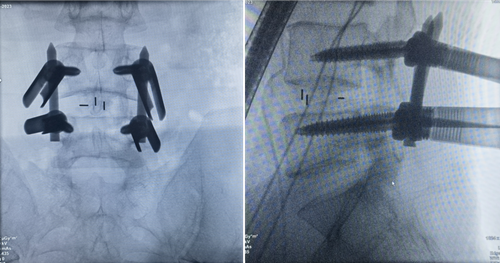

37岁的周先生是位尿毒症患者,疾病的折磨让这个本该血气方刚的年轻人变得弱不禁风,可屋漏偏逢连夜雨,腰椎间盘突出再让他羸弱的身体雪上加霜,因为腰腿痛,他甚至无法正常行走,疼痛严重影响着他的生活。患者基础疾病较重,对其而言,传统手术风险大。经仔细评估,李宇旭医生决定为患者实施UBE内镜下腰椎融合手术,手术非常顺利,术后患者下肢疼痛消失,如期恢复,术后第2天下床活动,术后3天即出院,周先生又像从前一样健步如飞了。

术后影像显示融合器内固定位置良好